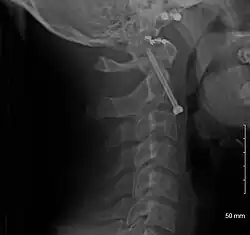

A fracture of the base of the dens as seen on plain X-ray -

A fracture of the base of the dens as seen on CT -

Type 3 odontoid fracture -

Type 2 dens fracture